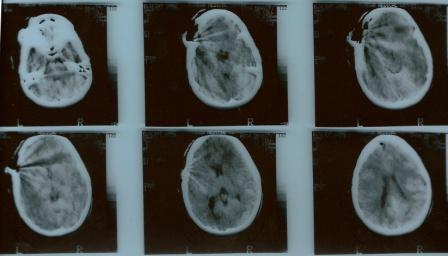

JS was born in 1974. At the age of 9½, she suffered injuries in a car accident in Israel. She broke her left arm and underwent a small skull injury above her left eyebrow. The top CT images were taken in  February 1984 at Rambam Medical Center, Haifa, Israel. They demonstrate acute left frontal skull fracture.

The result came as a shock to JS: Encephalomalacia in the left frontal lobe and mild T2 hyperintensity within the left middle frontal gyri. These anomalies were minor but consequential. They partly (if not fully) accounted for the behavioral anomalies that had prompted this imaging investigation. In the following years, JS received social security support, first in Minnesota, later in California (where she had spent most of her childhood and part of her youth).

Deep wound on left forehead, from eyebrow to parietal area, pulsing dura exposed, subdural air. Operated under general anesthesia, small tear in dura, minimal contusion below. Wound closed without reconstruction of skull defect. Superficial consciousness for 2½ days. Release after 8 days, no overt neurological deficits.

This last remark stirred hopes in the family that JS, then 9½ years old and such a beautiful and charming girl, would have been lucky and would recover fully from this severe incident. But the neurosurgeon should have known better. He had seen pieces of broken bone, subdural air, and the small tear in the dura. These observations leave little doubt that the injury had affected not only the skull but also the brain tissue below. And behind the eyebrow lies the orbitofrontal cortex, getting its name by its tight contact with the orbit, the bony cavity harboring the eye. It is no surprise that another deficit remaining from this injury was a partial loss of eyesight on the left side.